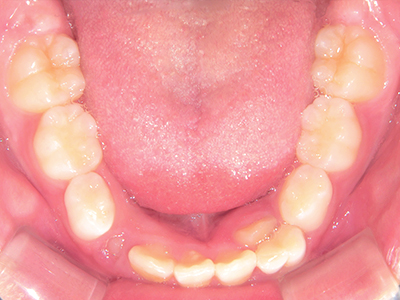

↓ - 下あごが狭くなる・下あごの位置が悪くなる

↓ - さまざまな不正咬合が生じる

ないき歯科クリニックでは、上あごの成長不足を補い、鼻呼吸を獲得しつつ歯列を整え、将来のお口をより健康な状態にすることをゴールに定める矯正治療をおこなっています。